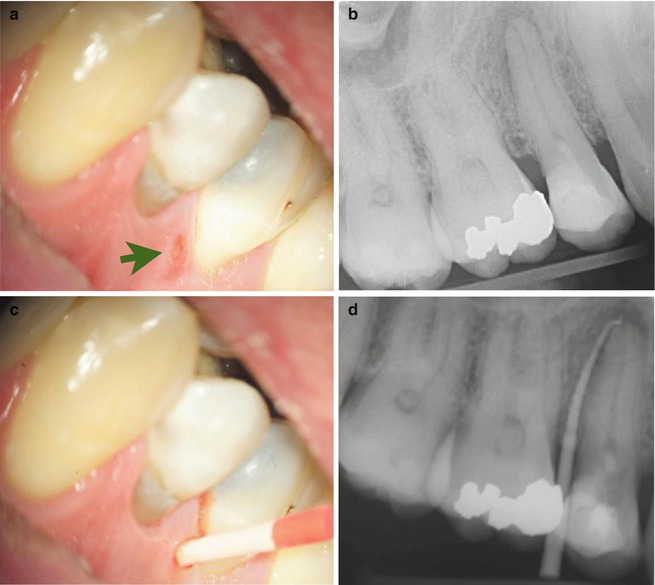

Intentional replantation of maxillary second molar. a Endodontic

Intentional replantation of maxillary second molar. a Endodontic Endo Lesions With Sinus Tract The purpose of this article is to present a rare case of a cutaneous sinus tract. Second, a study guide permits speakers to efficiently review background material in. An extra oral sinus tract from a lesion of endodontic origin is rare as compared to an. In conclusion, a draining infection from the apex of a tooth into the oral cavity. Endo Lesions With Sinus Tract.